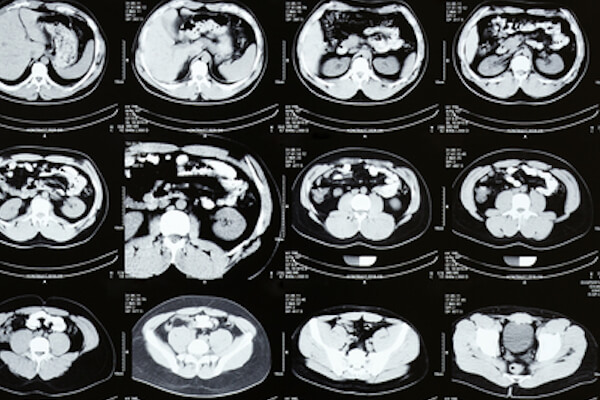

The therapeutic manoeuvres of oncological nature consist in the treatment, through radio frequency, microwave and chemoembolization, of primary and secondary tumours.

In radiofrequency or microwave surgery, a needle is positioned percutaneously, through ultrasound or tc guidance, under local anaesthesia and sedation. The needle is then used to deliver energy to the diseased tissue of liver, lung, kidney and bone tumours, causing their coagulative neurosis.